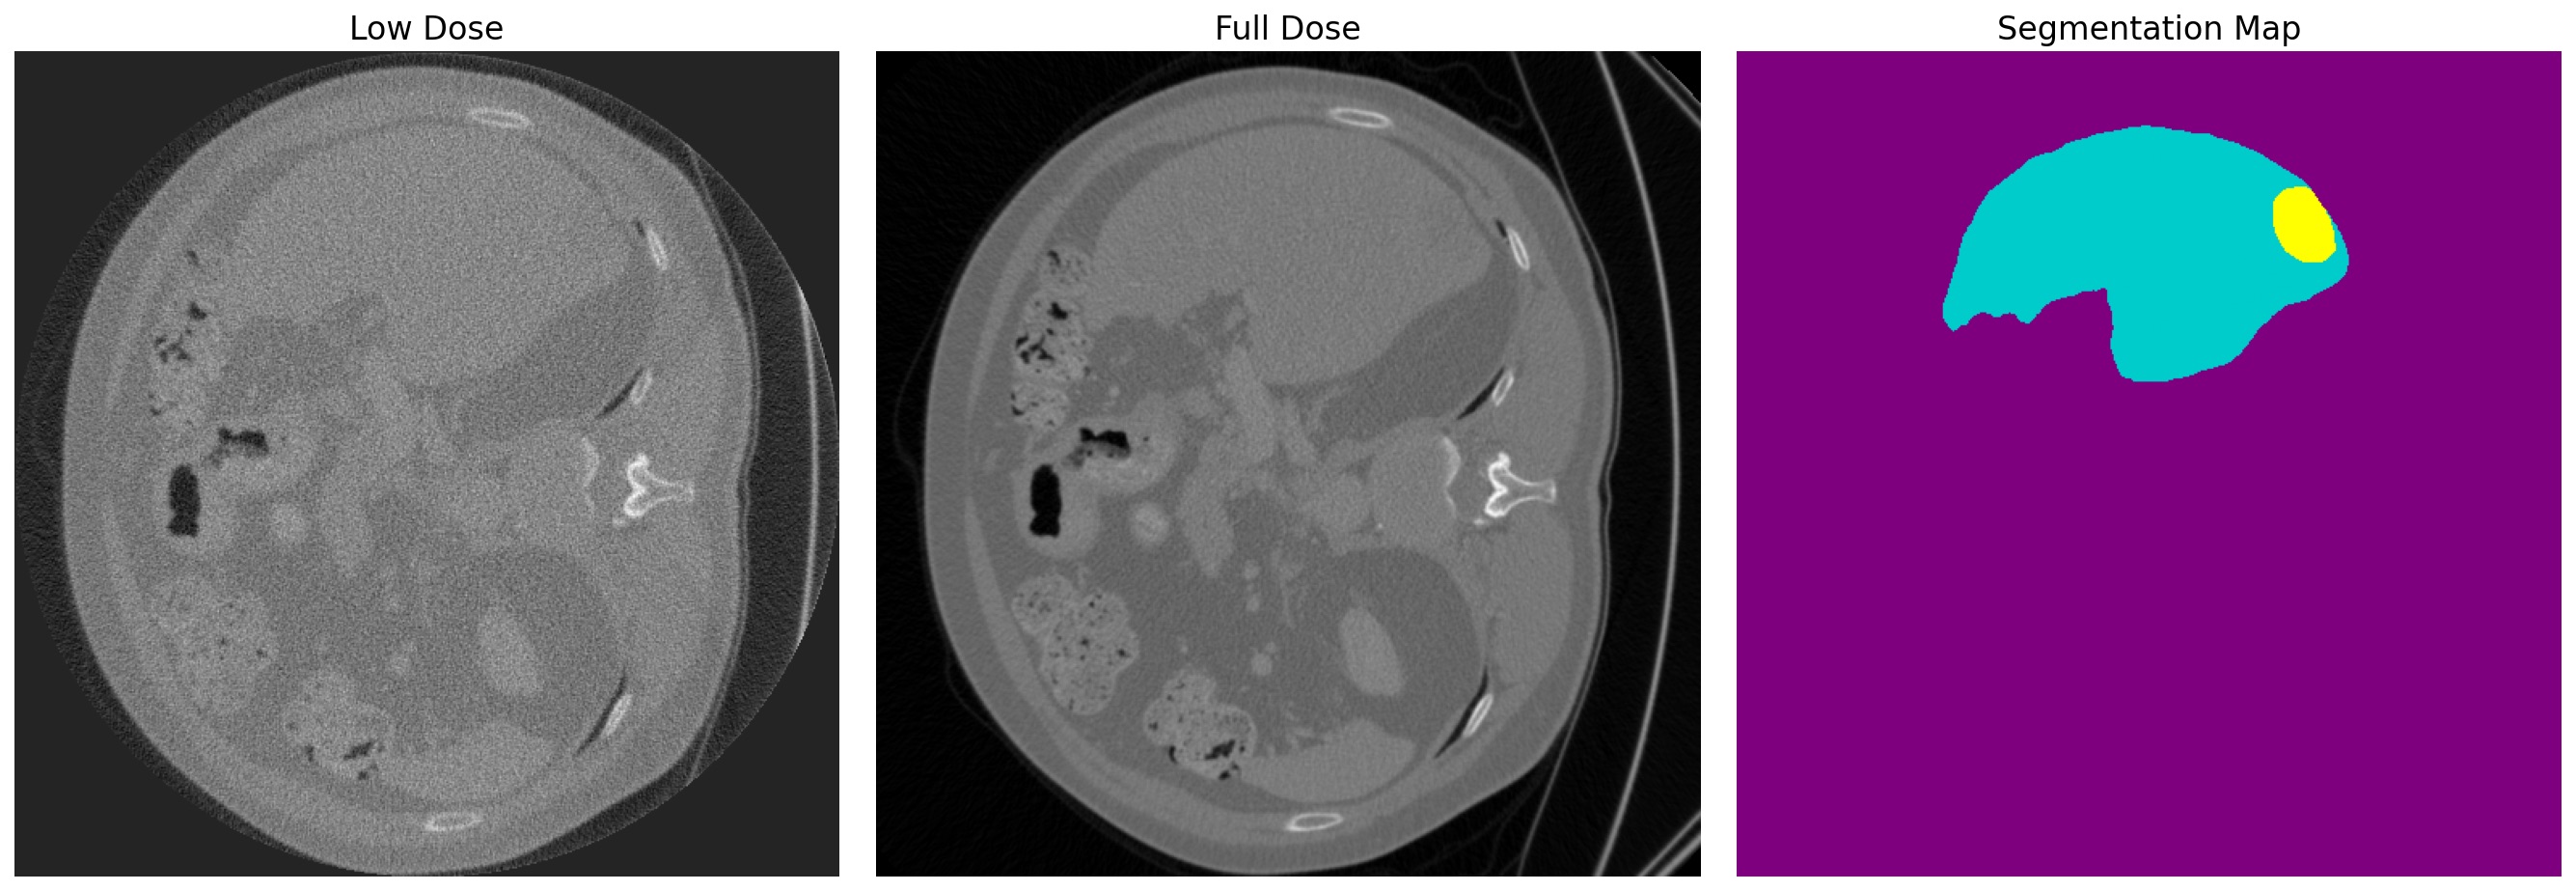

The preprocessing step yielded 19163 CT slice pairs, each consisting of a low-dose scan, its corresponding full-dose scan, and an associated non-empty segmentation map. During preprocessing, the image resolution was set to 512x512 pixels. We split the dataset 80% for training and 20% for testing purposes. Fig. 2 shows a sample from this preprocessed dataset.

For performance evaluation, we first decided to test our task-adaptive models’ performances in PSNR and SSIM metrics to observe, how they compare with other models according to traditional evaluation approaches. To evaluate reconstruction performances, PSNR and SSIM were computed within a circular region of interest (ROI) area with a 256-pixel radius, centered on the 512x512 scans. This masking was necessary because the simulation methodology only generates data within this circular region. Consequently, the areas outside ROI are diagnostically irrelevant and appear uniformly gray, as illustrated in the low-dose scan in Fig. 2.